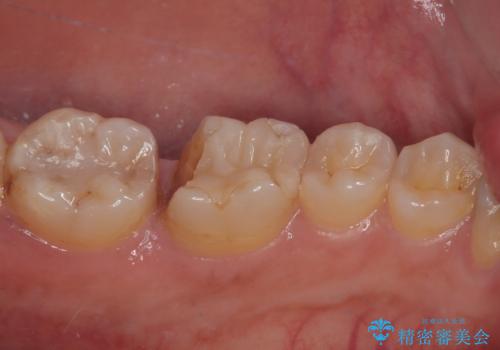

- 左下の詰め物が割れたとのことで来院された患者様です。現在に至るまで二度セラミックの詰め物(セラミックインレー)が割れているので強度面を考慮しセラミックの被せもの(セラミッククラウン)にて治療を行っていくことにしました。

拡大鏡視野下でセラミックインレー、虫歯の除去を行い、オールセラミッククラウンに適した形に整えました。

型どりはシリコーンゴムを用いて精密印象を行っています。